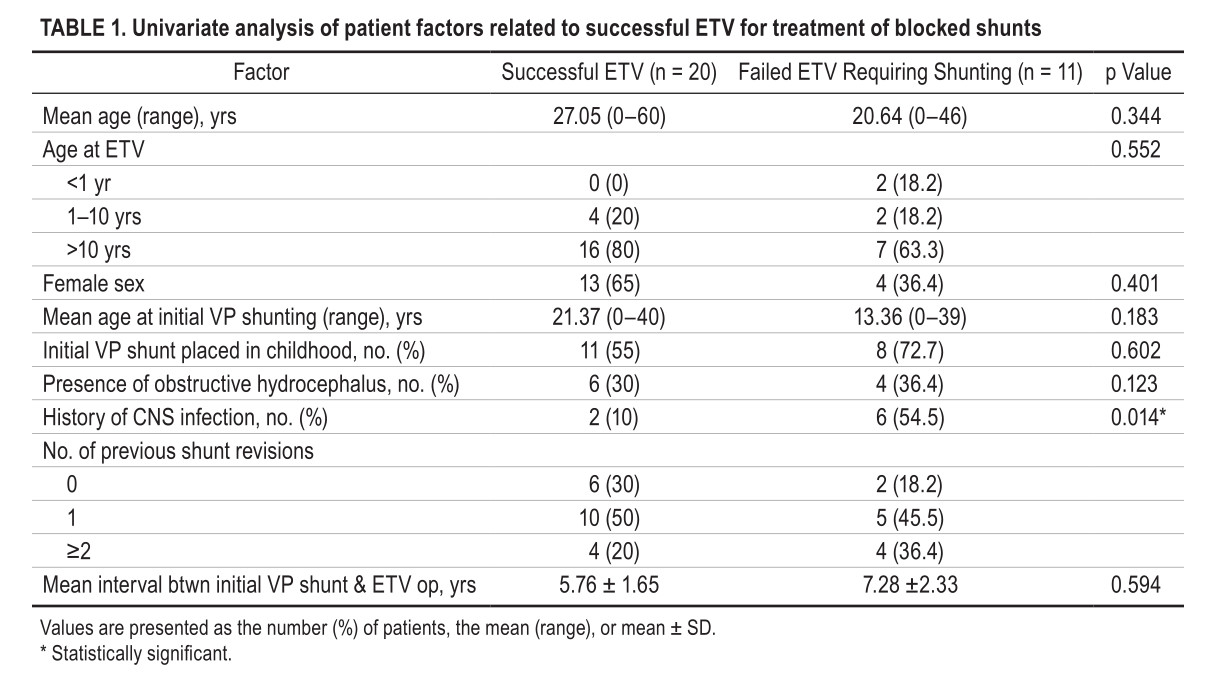

脑积水合并脑室腹腔分流(VP分流)术后梗阻是一种危及生命的疾病。急诊内镜下进行第三脑室造瘘术(ETV)可作为一种治疗方式。这项研究的目的是确定与ETV治疗VP分流后梗阻患者的失败相关的独立危险因素。作者回顾性分析2000年~2016年因VP分流管堵塞而接受ETV治疗的患者的临床资料。对年龄、性别、中枢神经系统(CNS)感染史、既往分流手术次数、作为急症或择期手术进行的手术、专家人数以及其他因素,进行单变量和多变量分析,以确定与VP分流梗阻患者进行ETV后失败的相关的独立因素。结果,在研究期间,共有121名患者接受了ETV。在这些患者中,31名VP术后阻塞患者(25.6%)接受了ETV治疗。在这31例中有25例(80.6%)作为急症手术进行了ETV。急症手术成功率为(64%[成功/总数=16/25]),择期手术成功率为(66.7%[成功/总数=4/6];OR 0.062,95%CI 0.001-2.708;p=0.149),ETV的成功率在两者之间没有显著差异。单变量和多变量分析表明,CNS感染史是ETV失败的独立危险因素(OR 0.030,95%CI 0.001-0.888;p=0.043)。结论为,急症ETV的成功率与择期ETV相当。CNS感染史是ETV治疗分流后再堵塞患者的失败的独立预测因子。

图:中枢神经系统感染史直接影响了对VP分流后再梗阻患者进行内镜下第三脑室造瘘术的成功率。